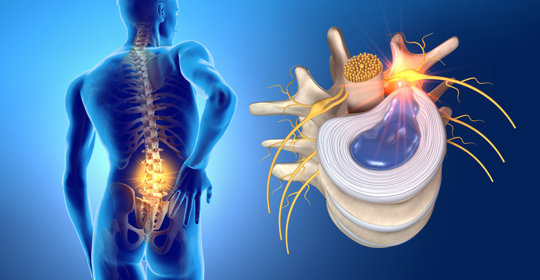

橋腦出血:中風復健方法與時間

橋腦出血:處理與預防措施

橋腦出血:治療措施與緊急性

橋腦出血:差異與治療